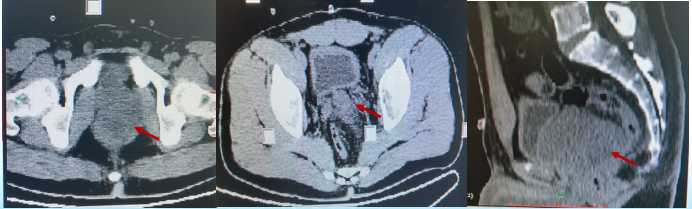

術(shù)前盆腔MRI:列腺大小6.3*7.3*6.4cm,前列腺癌可能,累及左側(cè)精囊

2019年2月全身PET-CT:前列腺惡性腫瘤(肉瘤?),左側(cè)精囊及中下段直腸受侵。

2019年12月盆腔及PETCT提示:左下肺及上肺轉(zhuǎn)移灶(2.5cm)左側(cè)盆腔結(jié)節(jié)(2.2cm)